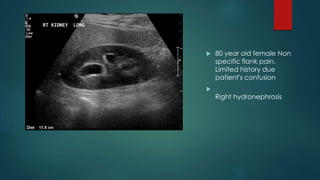

 80 year old female Non

specific flank pain.

Limited history due

patient's confusion



Right hydronephrosis